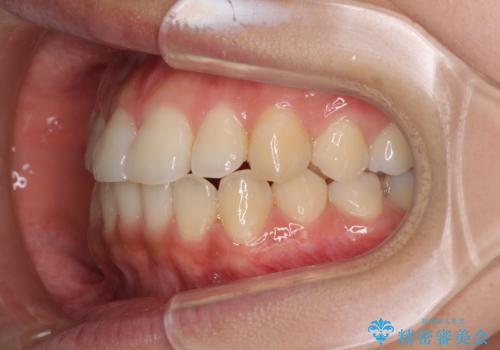

前歯の突出感とデコボコ インビザラインで改善

- 上下前歯のデコボコを気にして来院された患者様です。

インビザラインによる上下歯列の側方拡大と後方移動、IPR(歯と歯の間を削る)にるスペースの獲得により歯列を整えることとしました。

右上の小臼歯は歯根癒着をしており、様々な方法を試みるも動かすことができませんでした。

それでも奥歯のかみ合わせに不自由はなく、歯列をきれいに整えることができました。